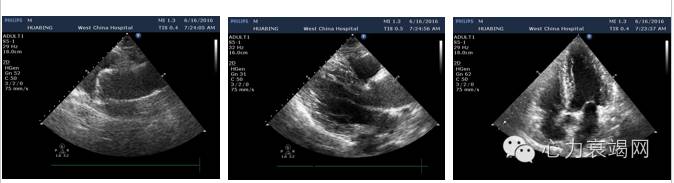

心脏彩超

1、左房稍大,余房室大小正常;主动脉明显增宽。主动脉弓降部近端未见明显异常。

2、室间隔明显增厚(IVS 14mm) ,左室后壁稍厚(LVPW 12mm),左室壁搏幅正常,未见明显室壁节段性运动异常。

3、左室流出道前向血流未见明显加速。

4、心包未见积液;

5、左室收缩功能侧值正常。